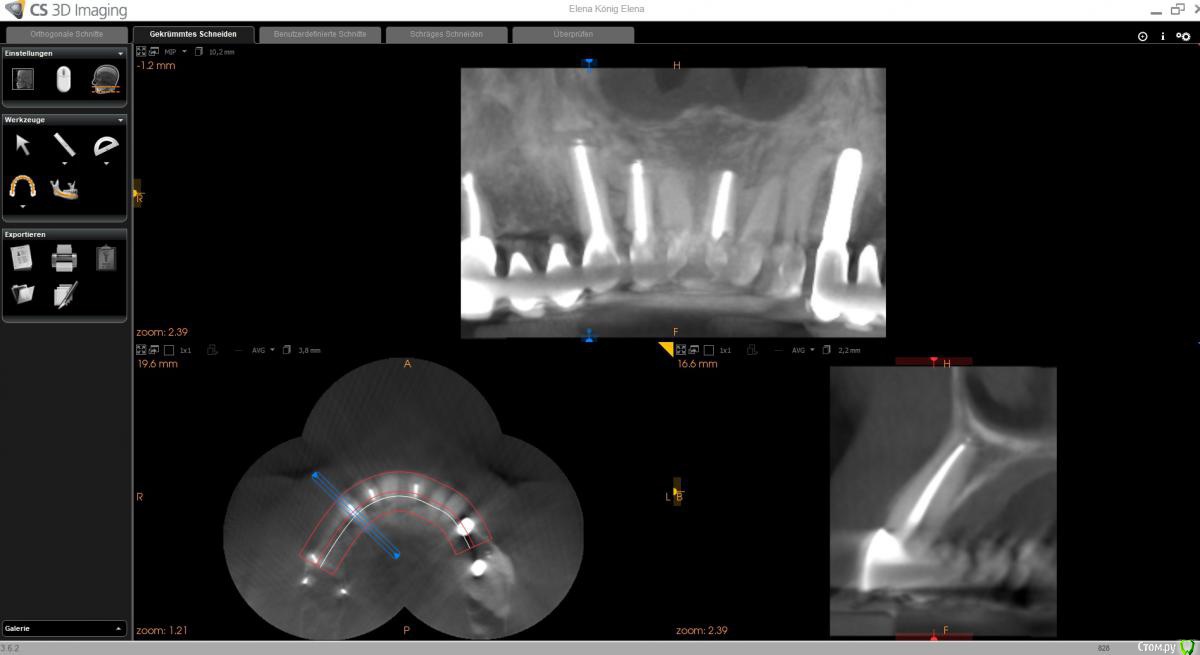

wladdX Опубликовано 10 февраля, 2020 Поделиться Опубликовано 10 февраля, 2020 (изменено) Вот ещё пара скриншотов. Очень непривычная для меня программа, так толком и не разобрался. Изменено 10 февраля, 2020 пользователем wladdX Ссылка на комментарий

Bier Опубликовано 10 февраля, 2020 Поделиться Опубликовано 10 февраля, 2020 Апекс зуба может открываться в мягкие ткани и тогда мы не увидим рентгенологически проблему. У меня была такая пациентка, РВК помогла. Ссылка на комментарий

wladdX Опубликовано 12 февраля, 2020 Поделиться Опубликовано 12 февраля, 2020 (изменено) Кстати, вот то, о чём говорил Bier, возможно, в этом причина. Изменено 12 февраля, 2020 пользователем wladdX Ссылка на комментарий